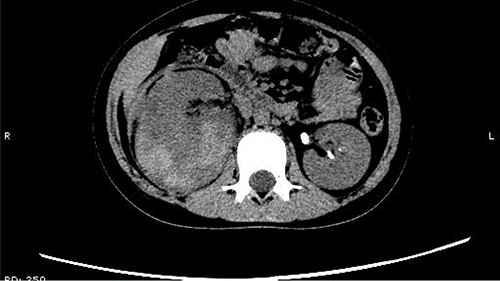

On 25 February, the patient complained of left back pain, nausea and vomiting. A further CT scan showed some irregular high-density shadows persisted in the left renal pelvis (Fig. 3) and an irregular high-density shadow was present in the left upper ureter (Fig. 4); furthermore, hydronephrosis was apparent in the left renal pelvis. There were no abnormalities in the bladder.

An irregular high-density shadow was present in the left upper ureter.